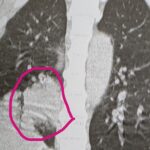

背中が痛い男性

2025年12月2日

総合診療医

60代の男性です。 1か月前から背中が痛くて、近くの整形外科に受診しました。 レントゲンで異常なく、筋肉痛と言われました。 よくならないために、当院に受診し CTをとったところ、右肺に大きな腫瘍を認め、総合病院にご紹介になりました。 背中が痛いのは、整形外科ではなく 総合診療かかりつけ医に受診が必要です。 一番怖い病気をまず否定することを、総合診療かかりつけ医は考えます。 視野広く、診療すること...